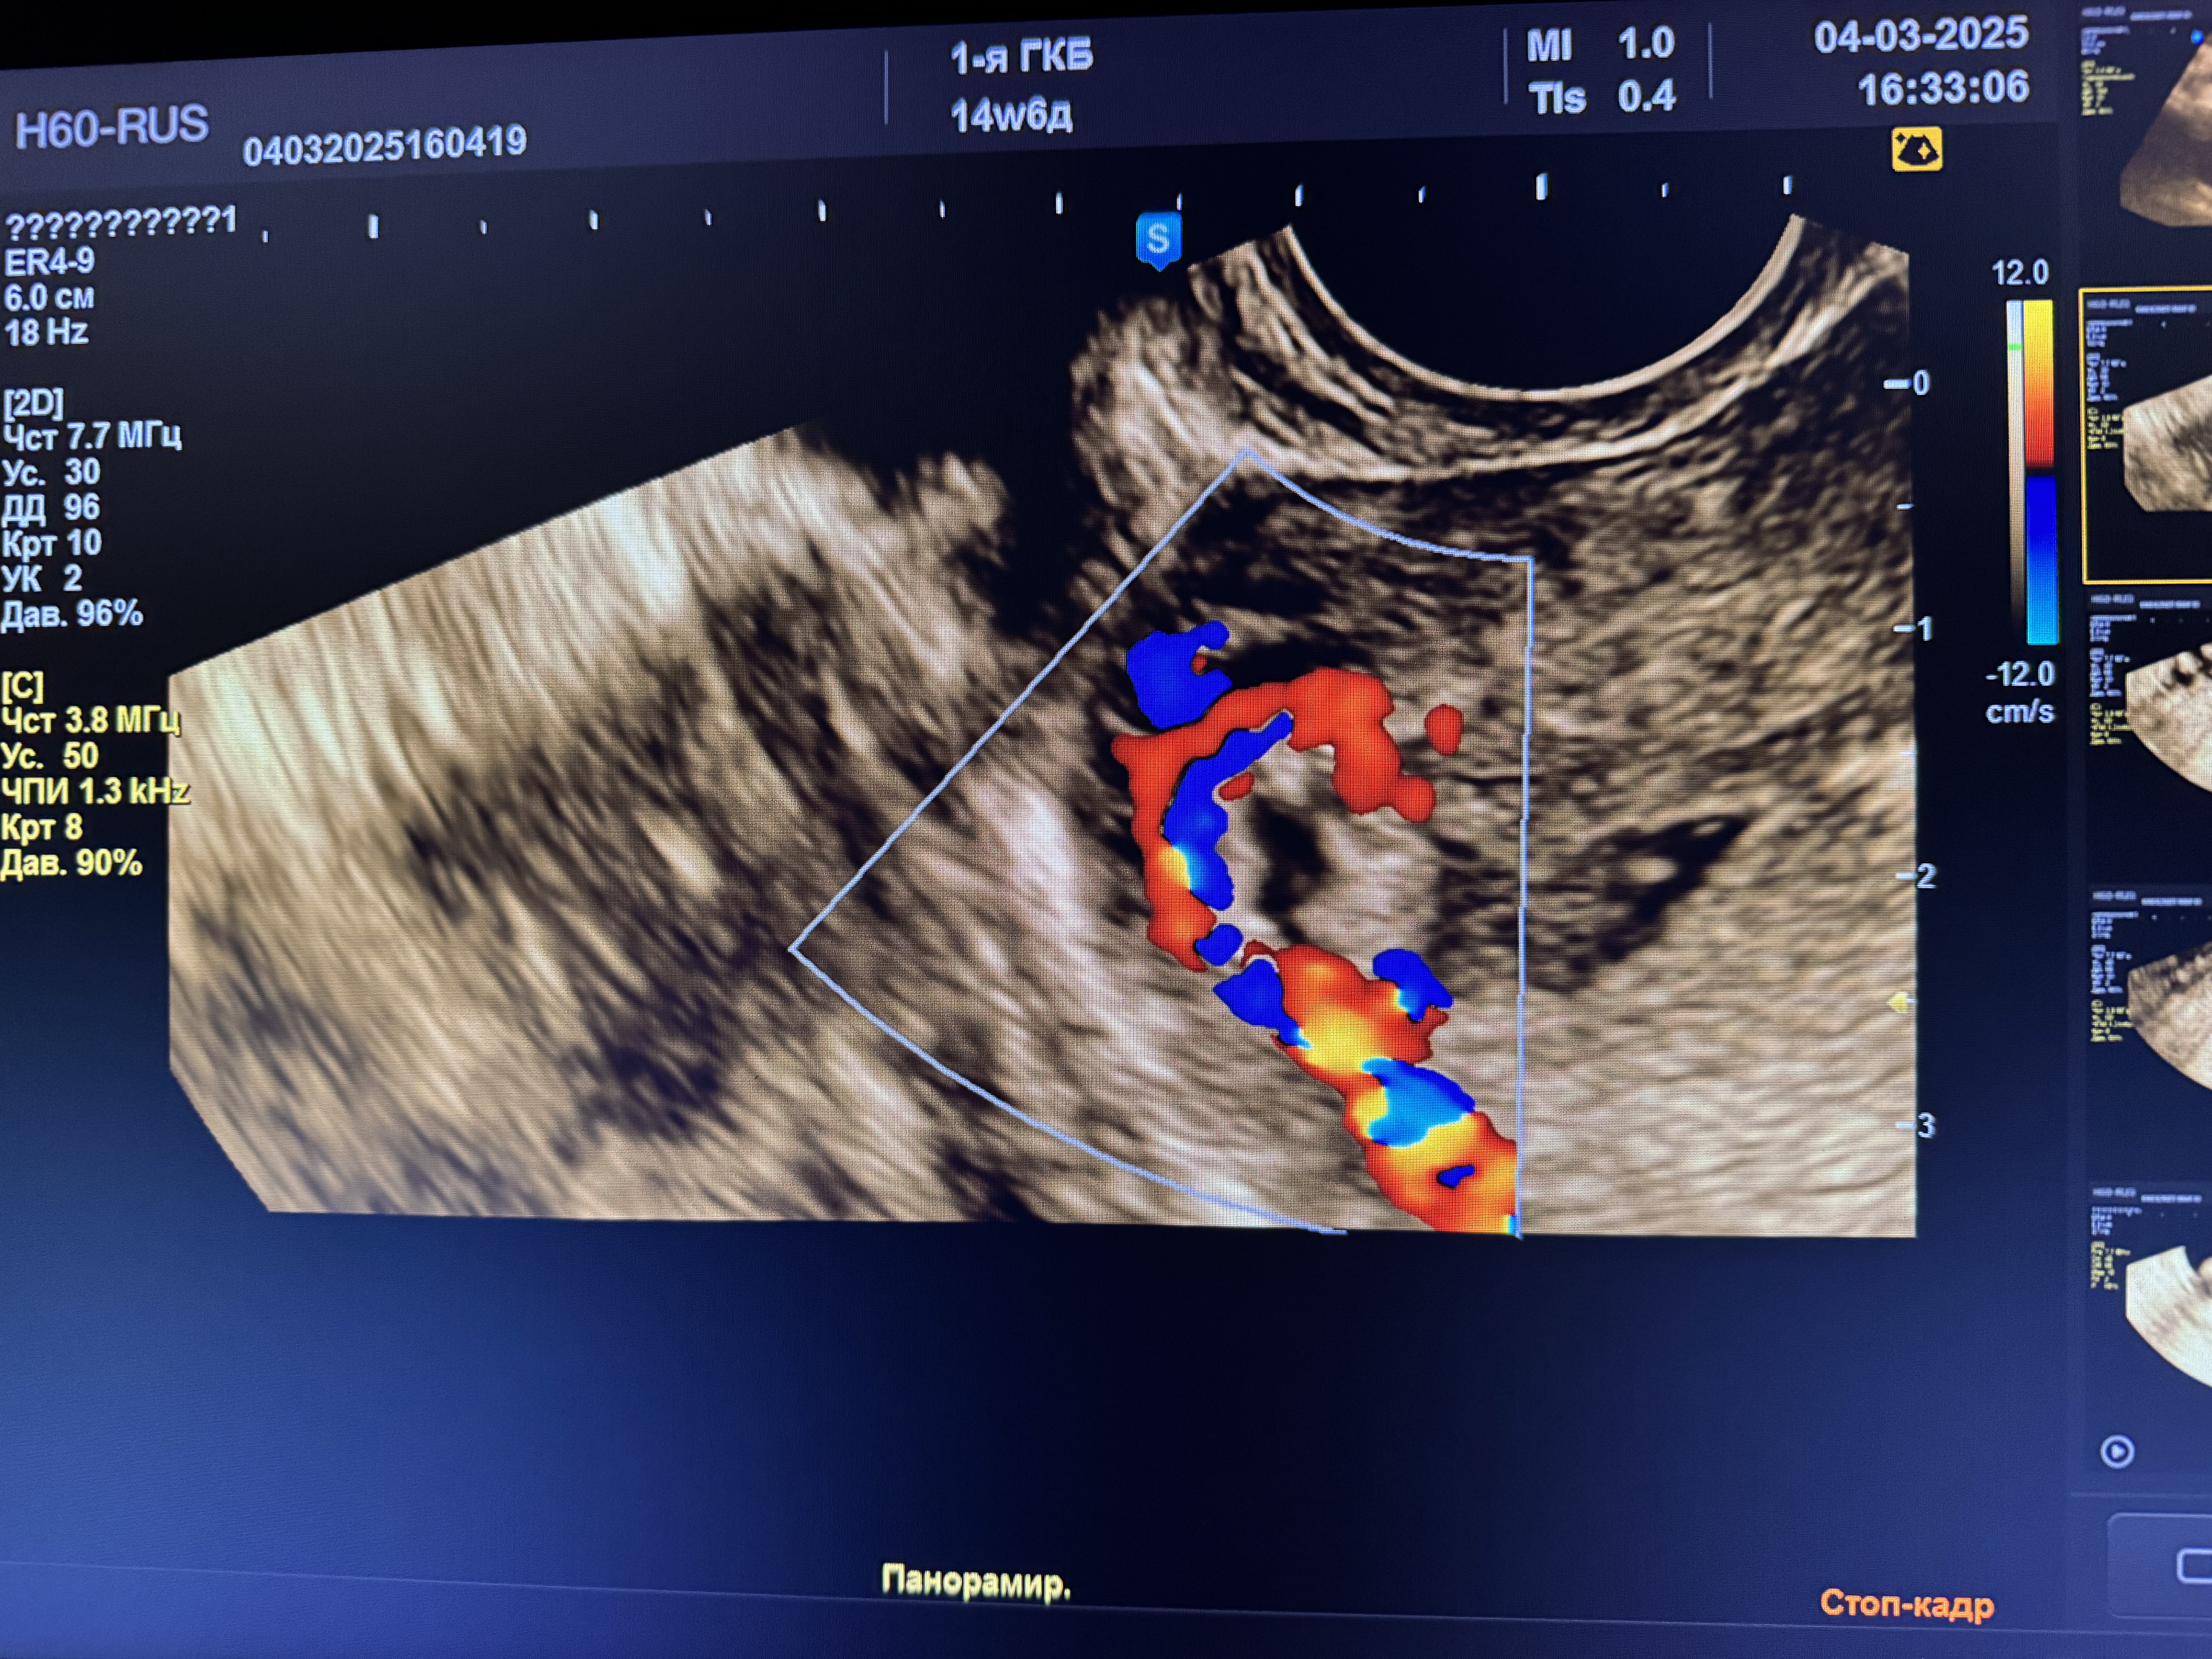

сделала 2.03 узи, нашли гематометру, остатки плодного яйца.

направили в стационар на чистку, сегодня сделали узи и подозревают новую беременность малого срока,а может и это от старой остатки, точно ответить мне не могут, хгч я сдавала от 27.02, 4254

Марина, добрый вечер, плодное яйцо вроде как и видят и хорион, врачи не могут ни подтвердить ни опровергнуть новую беременность,т.к если это она , то только все формируется, в любом случае, что-то со мной происходит, новая б на фоне старой, неполный пузырный занос или просто остатки старой беременности, конкретики нет, завтра назначена гистероскопия, пообщаюсь с врачом .. обновлю свой дневник, 99%, что будут делать выскабливание , а там ждать гистологию